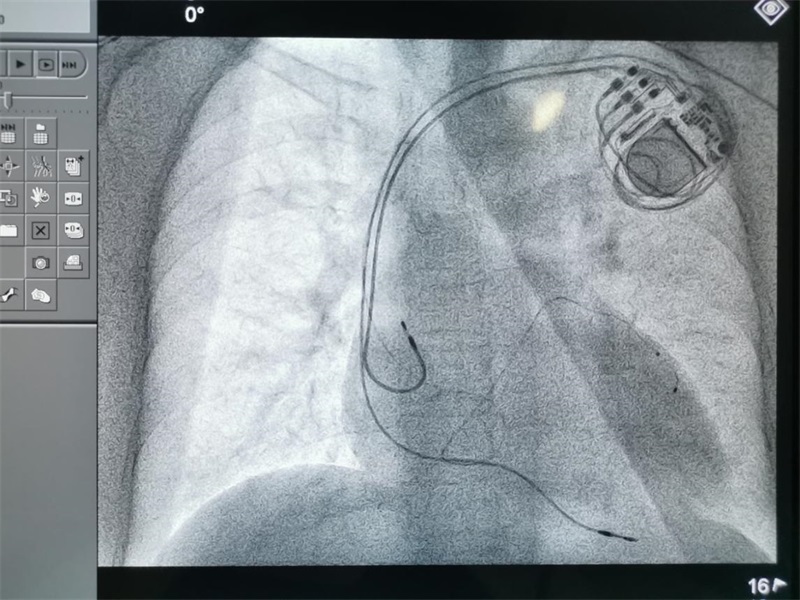

术前,彭小平教授积极与影像科联系、沟通,根据患者心脏CT图像三维重建,通过3D打印技术,立体展示冠状静脉各分支以及心腔的空间结构,重建带有冠状静脉分支的心脏立体模型,精确指导左、右心室电极、心房电极植入位置。手术过程中,术者在3D打印心脏模型精准指导下,将左室冠状窦电极精准定位于冠状静脉左室外膜面分支,右室螺旋电极及心房电极分别定位于右室心尖部及右心耳,最后连接起搏脉冲发射器。因有了3D打印心脏模型的指导,手术较平时手术较少了近30分钟。

该院心内科彭小平教授等人的最新研究发现,左、右心室电极植入位置间距离与 CRT 效果相关,CRT术中左、右心室电极植入位置越大,相应临床效果越佳,左、右心室电极植入位置间距离是 CRT 效果独立影响因素,此项研究成果获2019年我院临床优秀新技术一等奖。但是电极在冠状静脉分支、心室、心房的精确定位是影响CRT手术效果的重要因素,特别是如何在术前重建冠状静脉窦及其分支走形显得尤其重要。

“3D打印心脏模型不仅可以重建心房心室,而且可以清晰显示心脏冠状窦及其分支血管的走形,为术中寻找合适的电极位置提供了极大的帮助,将有助于缩短手术时间,提高手术的安全性和成功率,提高术后CRT反应性及疗效。”彭小平教授介绍道。